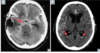

77

Diagnosis?

Epidural hematoma

78

Most likely cause?

Rupture of the **middle meningeal artery**; often secondary to pterion skull fracture

79

Subdural hematoma

80

Etiology/cause?

**Rupture of bridging veins** (can be acute or chronic) * Hemorrhage crosses suture lines; poor prognosis

81

Subarachnoid hemorrhage

82

Bleeding due to trauma or rupture of aneurysm or AV malformation

83

Intraparenchymal hemorrhage

84

Most common etiology/cause?

Most commonly caused by **systemic hypertension**